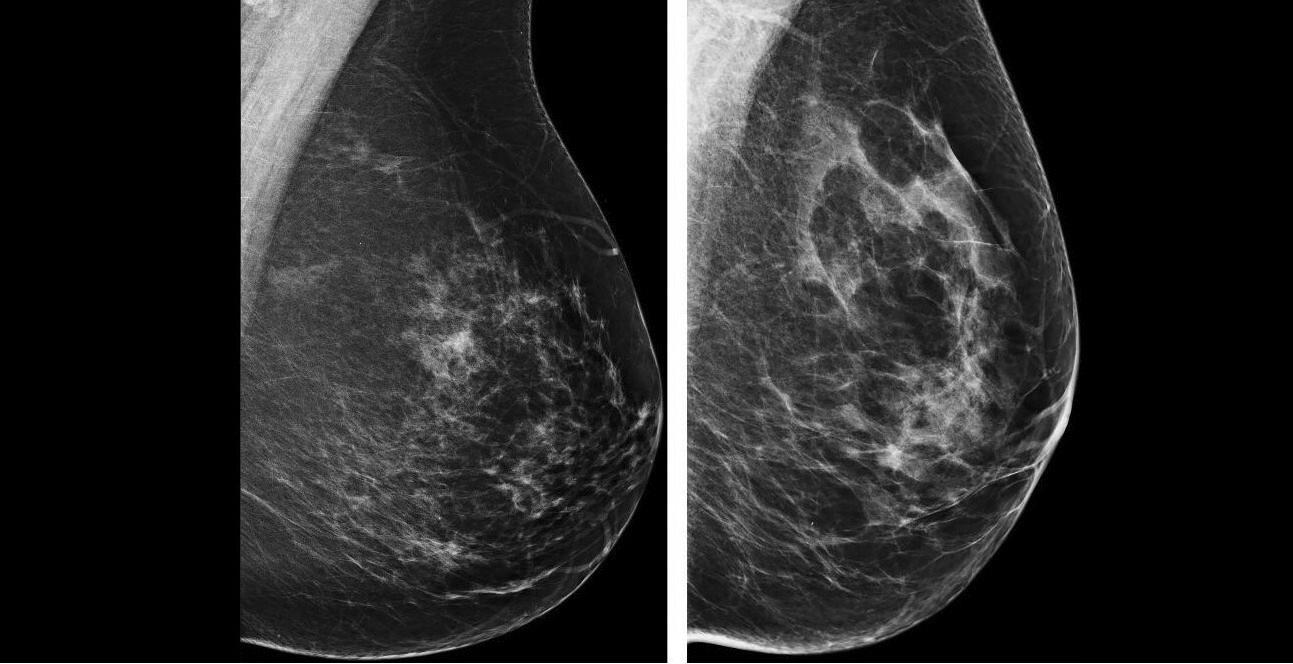

Aux Pays-Bas, des chercheurs de l’hôpital universitaire de Nijmegen ont réalisé une étude pour évaluer la capacité de l'intelligence artificielle (IA) à identifier les cancers du sein cliniquement pertinents, en utilisant les résultats du dépistage par mammographie. Ils ont comparé l’IA en tant que lecteur autonome et en tant que deuxième lecteur avec la lecture humaine unique et la double lecture humaine afin de déterminer l’impact potentiel de ces différentes configurations sur la détection du cancer. Les résultats de leurs travaux ont été publiés au mois d’août dans la revue Lancet Digital Health. [1]

Dans cette étude de cohorte rétrospective, les chercheurs ont inclus 42 236 mammographies de 42 100 femmes ayant participé au programme néerlandais de dépistage du cancer du sein entre le 1er septembre 2016 et le 31 août 2018. Les résultats concernant les cancers détectés étaient disponibles avec un suivi de 4 ans. Pour cette analyse, les images ont été traitées avec le